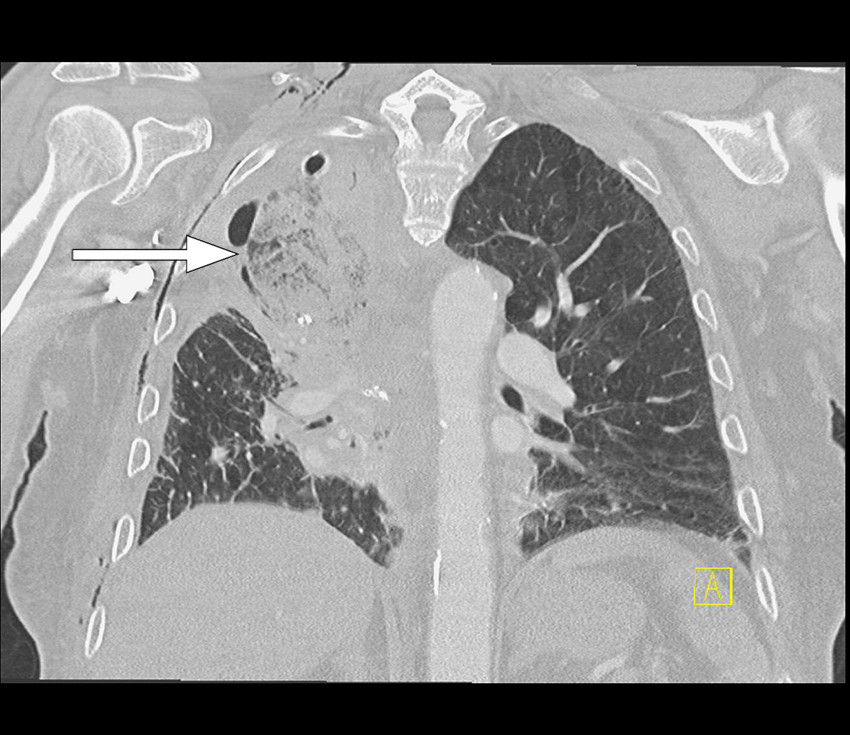

Rutinemessig postoperativ røntgen toraks viste atelektasepregede fortetninger i høyre lunges midtlapp. Det forelå også en liten høyresidig pneumotoraks og små mengder pleuravæske på samme side, som man kunne forvente etter operasjonen. Kontroll med røntgen toraks første postoperative dag viste økte fortetninger i øvre halvdel av høyre hemitoraks, som kunne være uttrykk for forverret atelektase, pleuravæske eller hemotoraks (figur 1). Pasienten var respiratorisk ubesværet og hadde god kapillær oksygenmetning på 96–98 % med oksygentilskudd 2 L/min på nesekateter. Det forelå ingen kliniske infeksjonstegn.

Grunnet tettere oppfølging ble røntgen toraks utført senere samme dag. Denne viste ikke vesentlig endring. Pasienten ble derfor henvist til CT-undersøkelse for videre diagnostikk. CT toraks med intravenøst kontrastmiddel utført på kveldstid samme dag viste en apikalt lokalisert midtlapp med utbredte mattglassfortetninger og områder med konsolidering samt fortykkede interlobulære septa (figur 2). Midtlappen fremsto som nærmest fullstendig devaskularisert. Proksimale midtlappsbronkus var obliterert, og transversale snitt viste subtilt virveltegn (swirl sign) i midtlappen som tegn på vridning. Fra radiologisk hold ble det reist mistanke om torsjon av midtlappen.